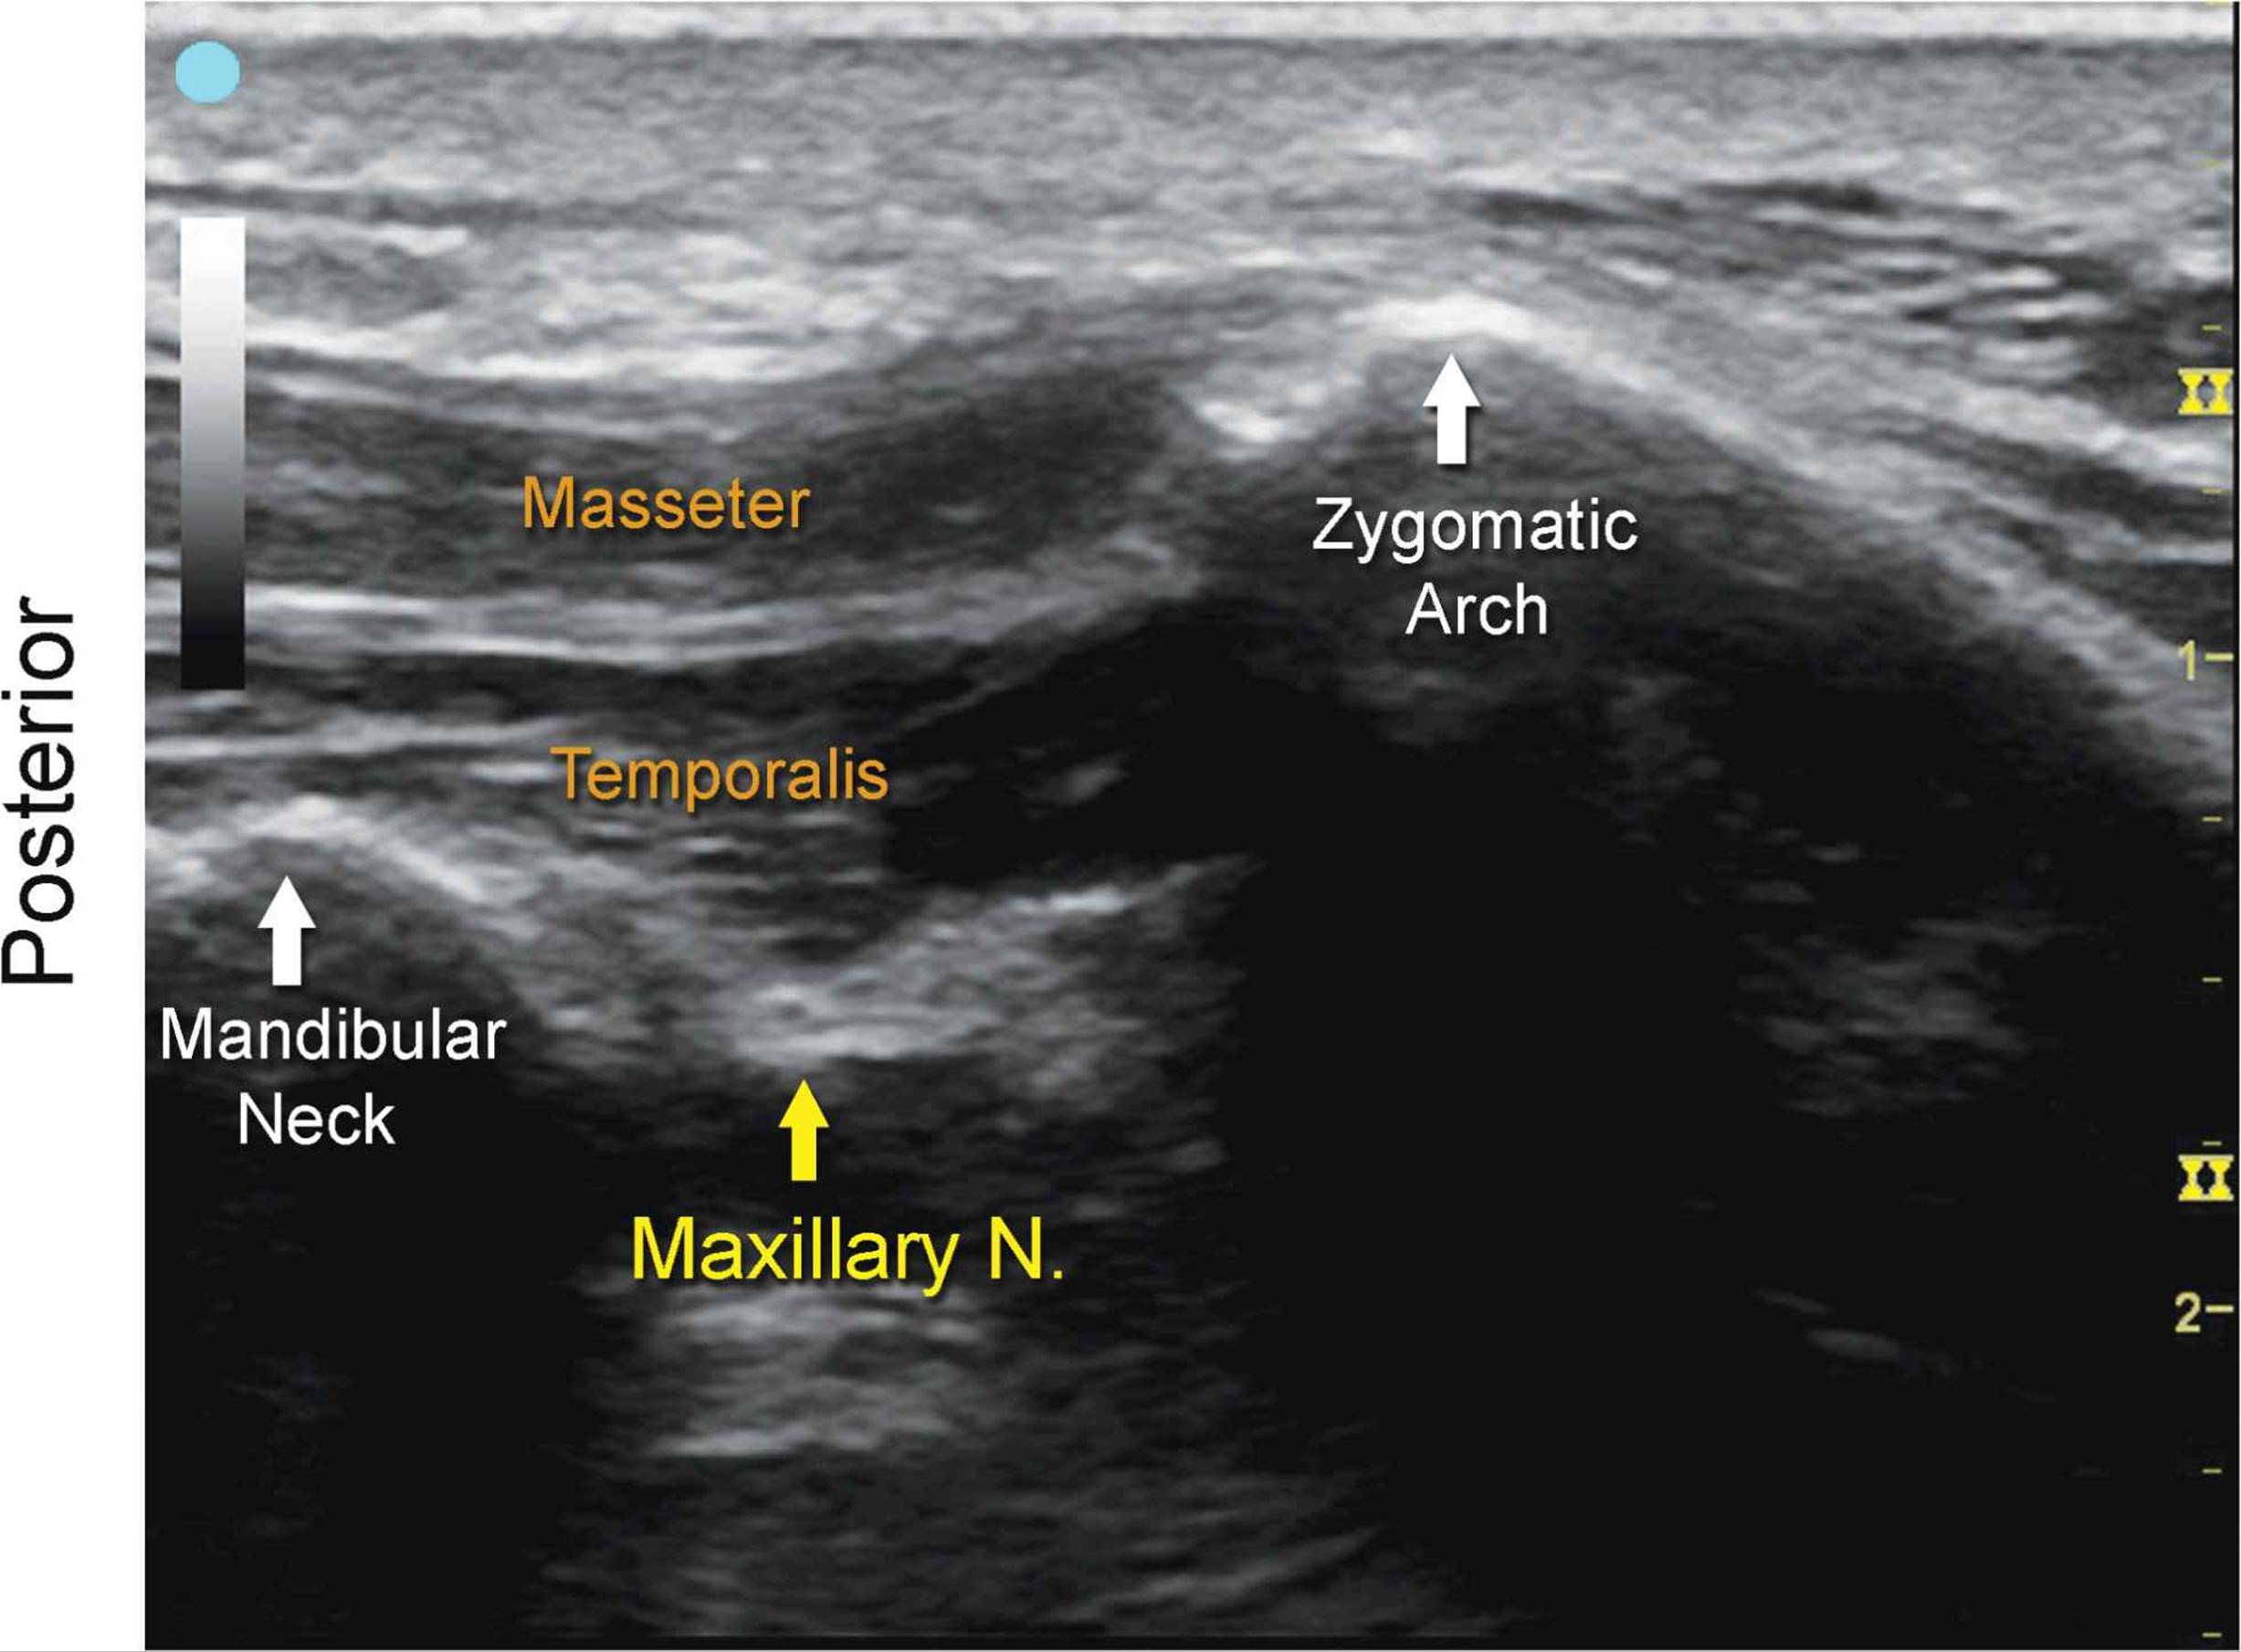

Maxillary Nerve

FIGURE 7.3.1A Ultrasound transducer position to image the maxillary nerve.

FIGURE 7.3.1B Ultrasound image of maxillary nerve.

FIGURE 7.3.1C Labeled ultrasound anatomy of maxillary nerve, transverse view.